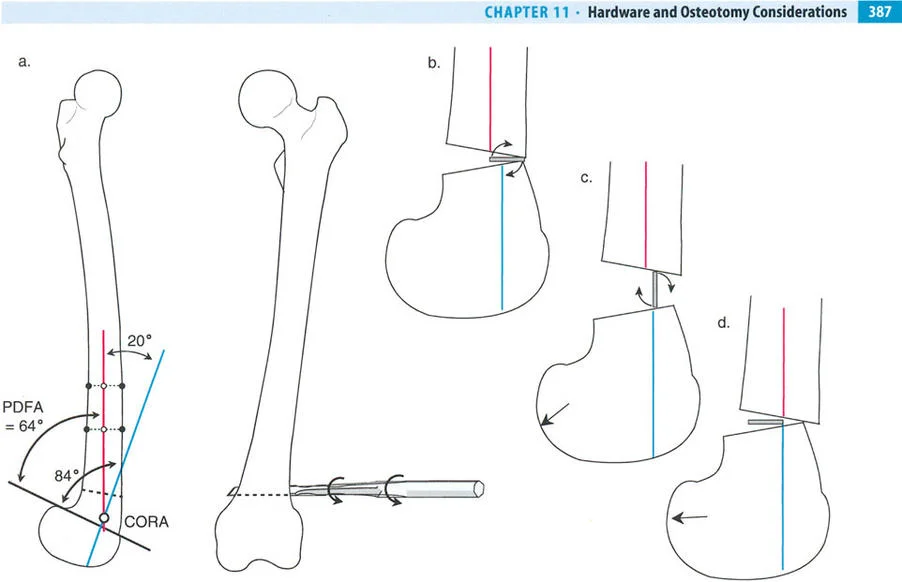

هذا الدليل الشامل يستعرض الاعتبارات الحاسمة لتطبيق الأجهزة، وتحديد مواضع المفاصل الاصطناعية (المفصلات)، وآليات الشد، والتسلسل الاستراتيجي للتصحيحات التدريجية. سواء كان الجراح يستخدم مثبتات إليزاروف الدائرية التقليدية، أو أنظمة الهيكسابود الحديثة (مثل جهاز تايلور الفراغي Taylor Spatial Frame)، أو المثبتات أحادية الجانب، فإن القواعد الهندسية التي تحكم مركز دوران الانحراف (CORA)، ومحور تصحيح الانحراف (ACA)، وانحراف المحور الميكانيكي (MAD) تظل مطلقة ولا تقبل الخطأ.

قواعد بالي لقطع العظم (Osteotomy Rules) في وضع الأجهزة

فهم قواعد بالي لقطع العظم أمر لا غنى عنه لتخطيط الإطار:

- قاعدة قطع العظم 1: عندما يمر قطع العظم ومحور تصحيح الانحراف (ACA) كلاهما عبر مركز دوران الانحراف (CORA)، فإن نهايات العظم ستنحرف دون ترجمة (انزياح). يتم استعادة المحور الميكانيكي، وتظل نهايات العظم متقاربة تمامًا، مما يخلق تصحيحًا كلاسيكيًا "إسفينيًا مفتوحًا" أو "إسفينيًا مغلقًا".

- قاعدة قطع العظم 2: عندما يمر محور تصحيح الانحراف (ACA) عبر مركز دوران الانحراف (CORA)، ولكن يتم إجراء قطع العظم على مستوى مختلف (غالبًا بسبب ضعف جودة العظم عند CORA أو مشاكل في الجلد)، فإن نهايات العظم ستنحرف وتخضع لترجمة محسوبة ومقصودة لإعادة محاذاة المحور الميكانيكي.

- قاعدة قطع العظم 3: (للاكمال) عندما يمر قطع العظم عبر مركز دوران الانحراف (CORA)، ولكن يتم وضع محور تصحيح الانحراف (ACA) خارج CORA، سيتم إنشاء تشوه ترجمة جديد، وهو خطأ شائع في وضع المفصلات غير المخطط له جيدًا.

في المنشآت القريبة من المفصل، غالبًا ما نعتمد على قاعدة قطع العظم 2. نظرًا لأنه لا يمكننا قطع العظم بأمان عند خط المفصل تمامًا (مركز دوران الانحراف CORA)، فإننا نقطع العظم في مستوى أدنى في منطقة الميتافيسيس. بعد تحقيق التصحيح الزاوي عبر المفصلات (محور تصحيح الانحراف ACA)، يتم إعادة محاذاة خطوط المحور الميكانيكي بشكل مثالي، ولكن نهايات العظم في موقع قطع العظم تتحرك بالنسبة لبعضها البعض.